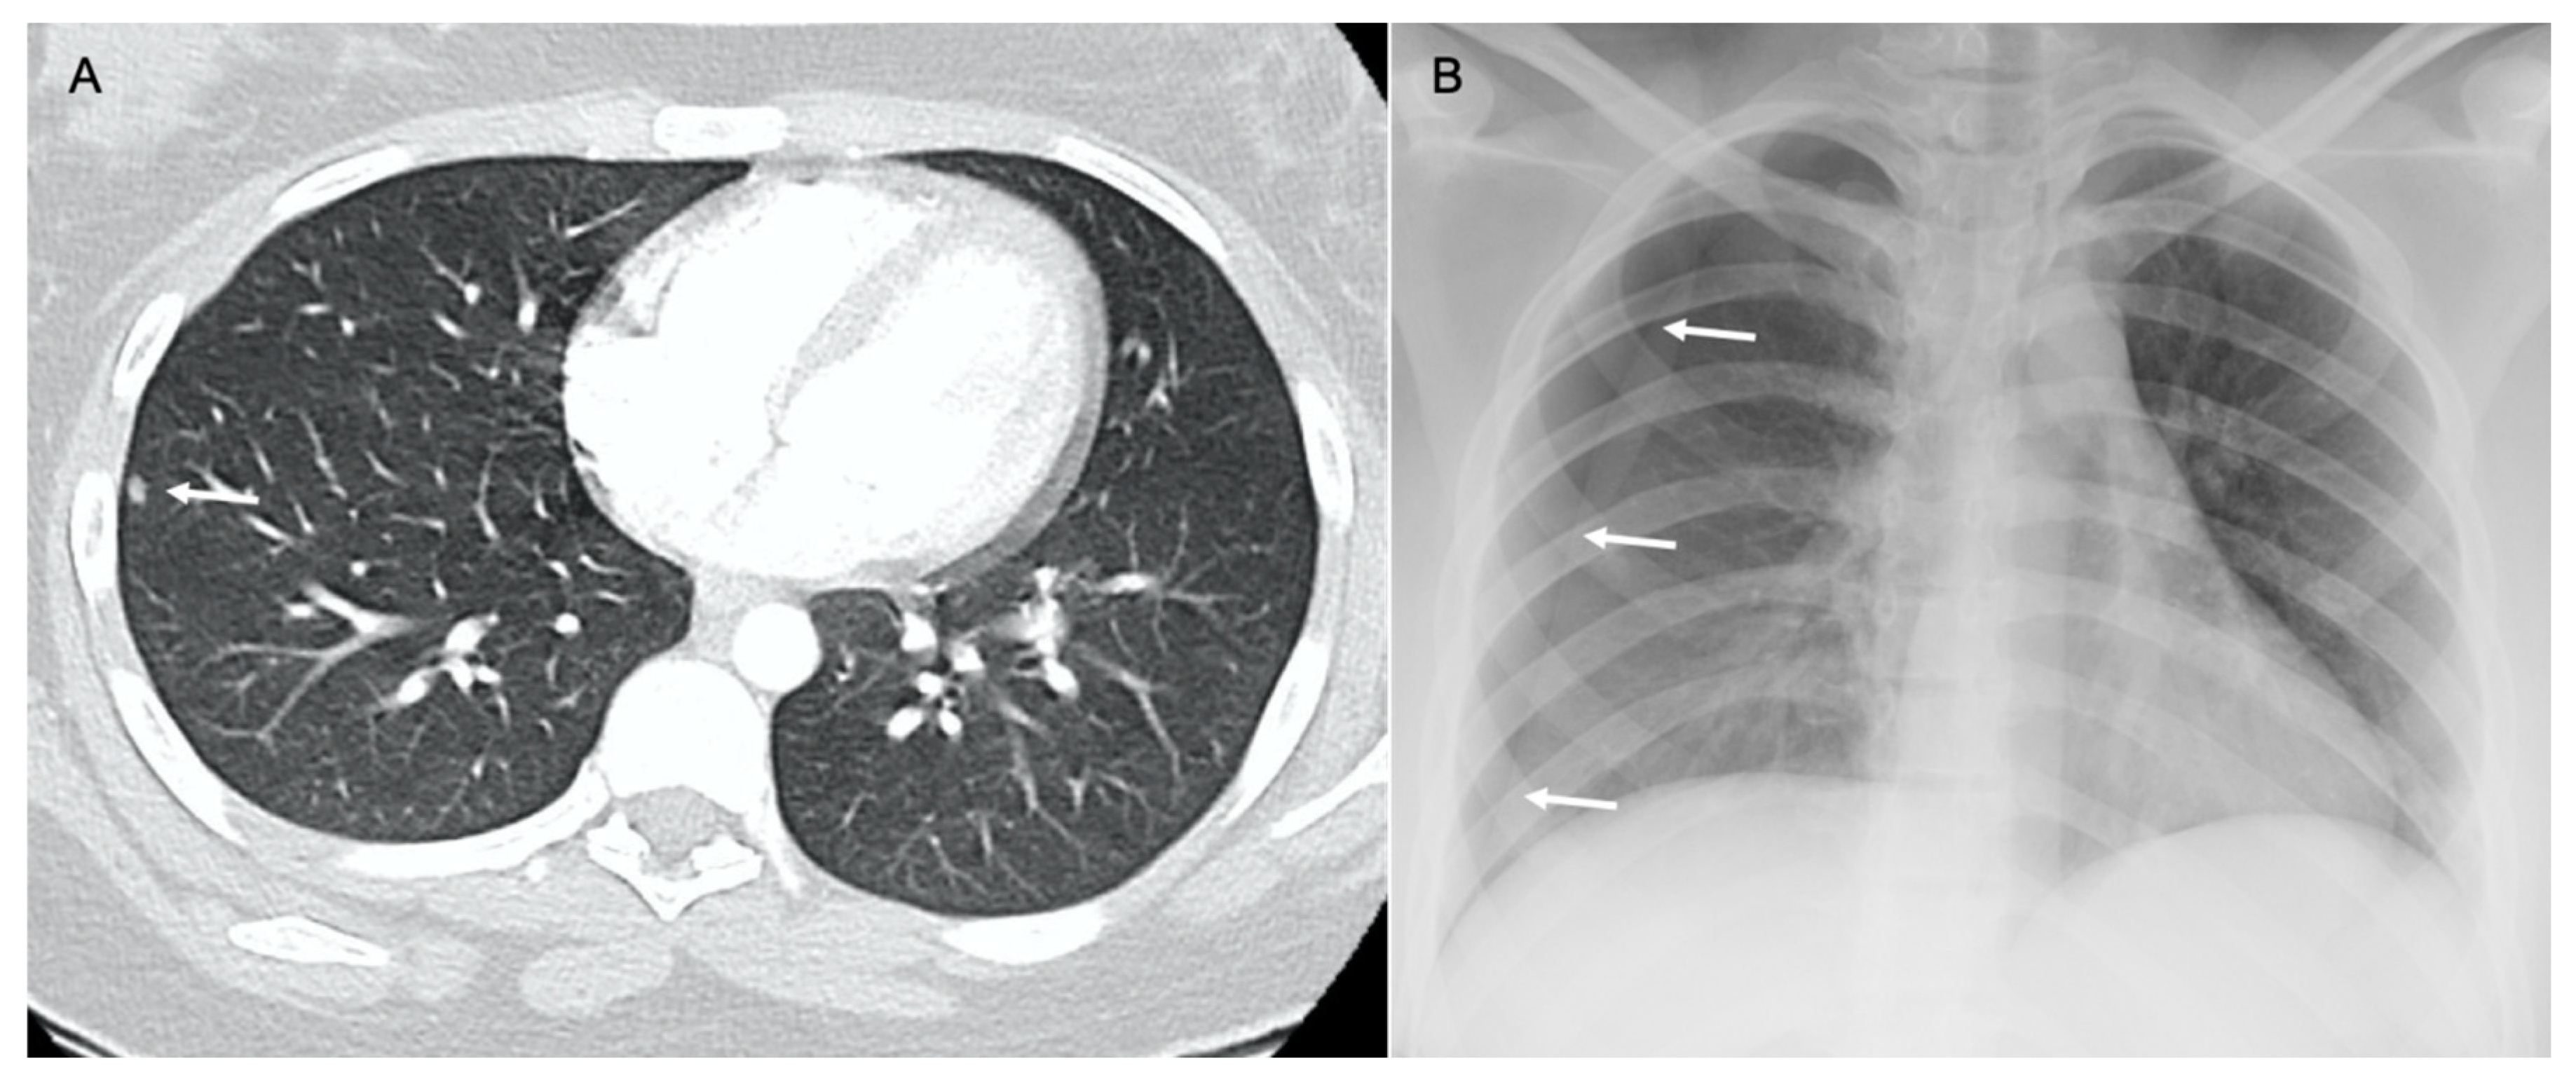

2.1. Parenchymal Metastasis

2.4. Lymphangitic Carcinomatosis